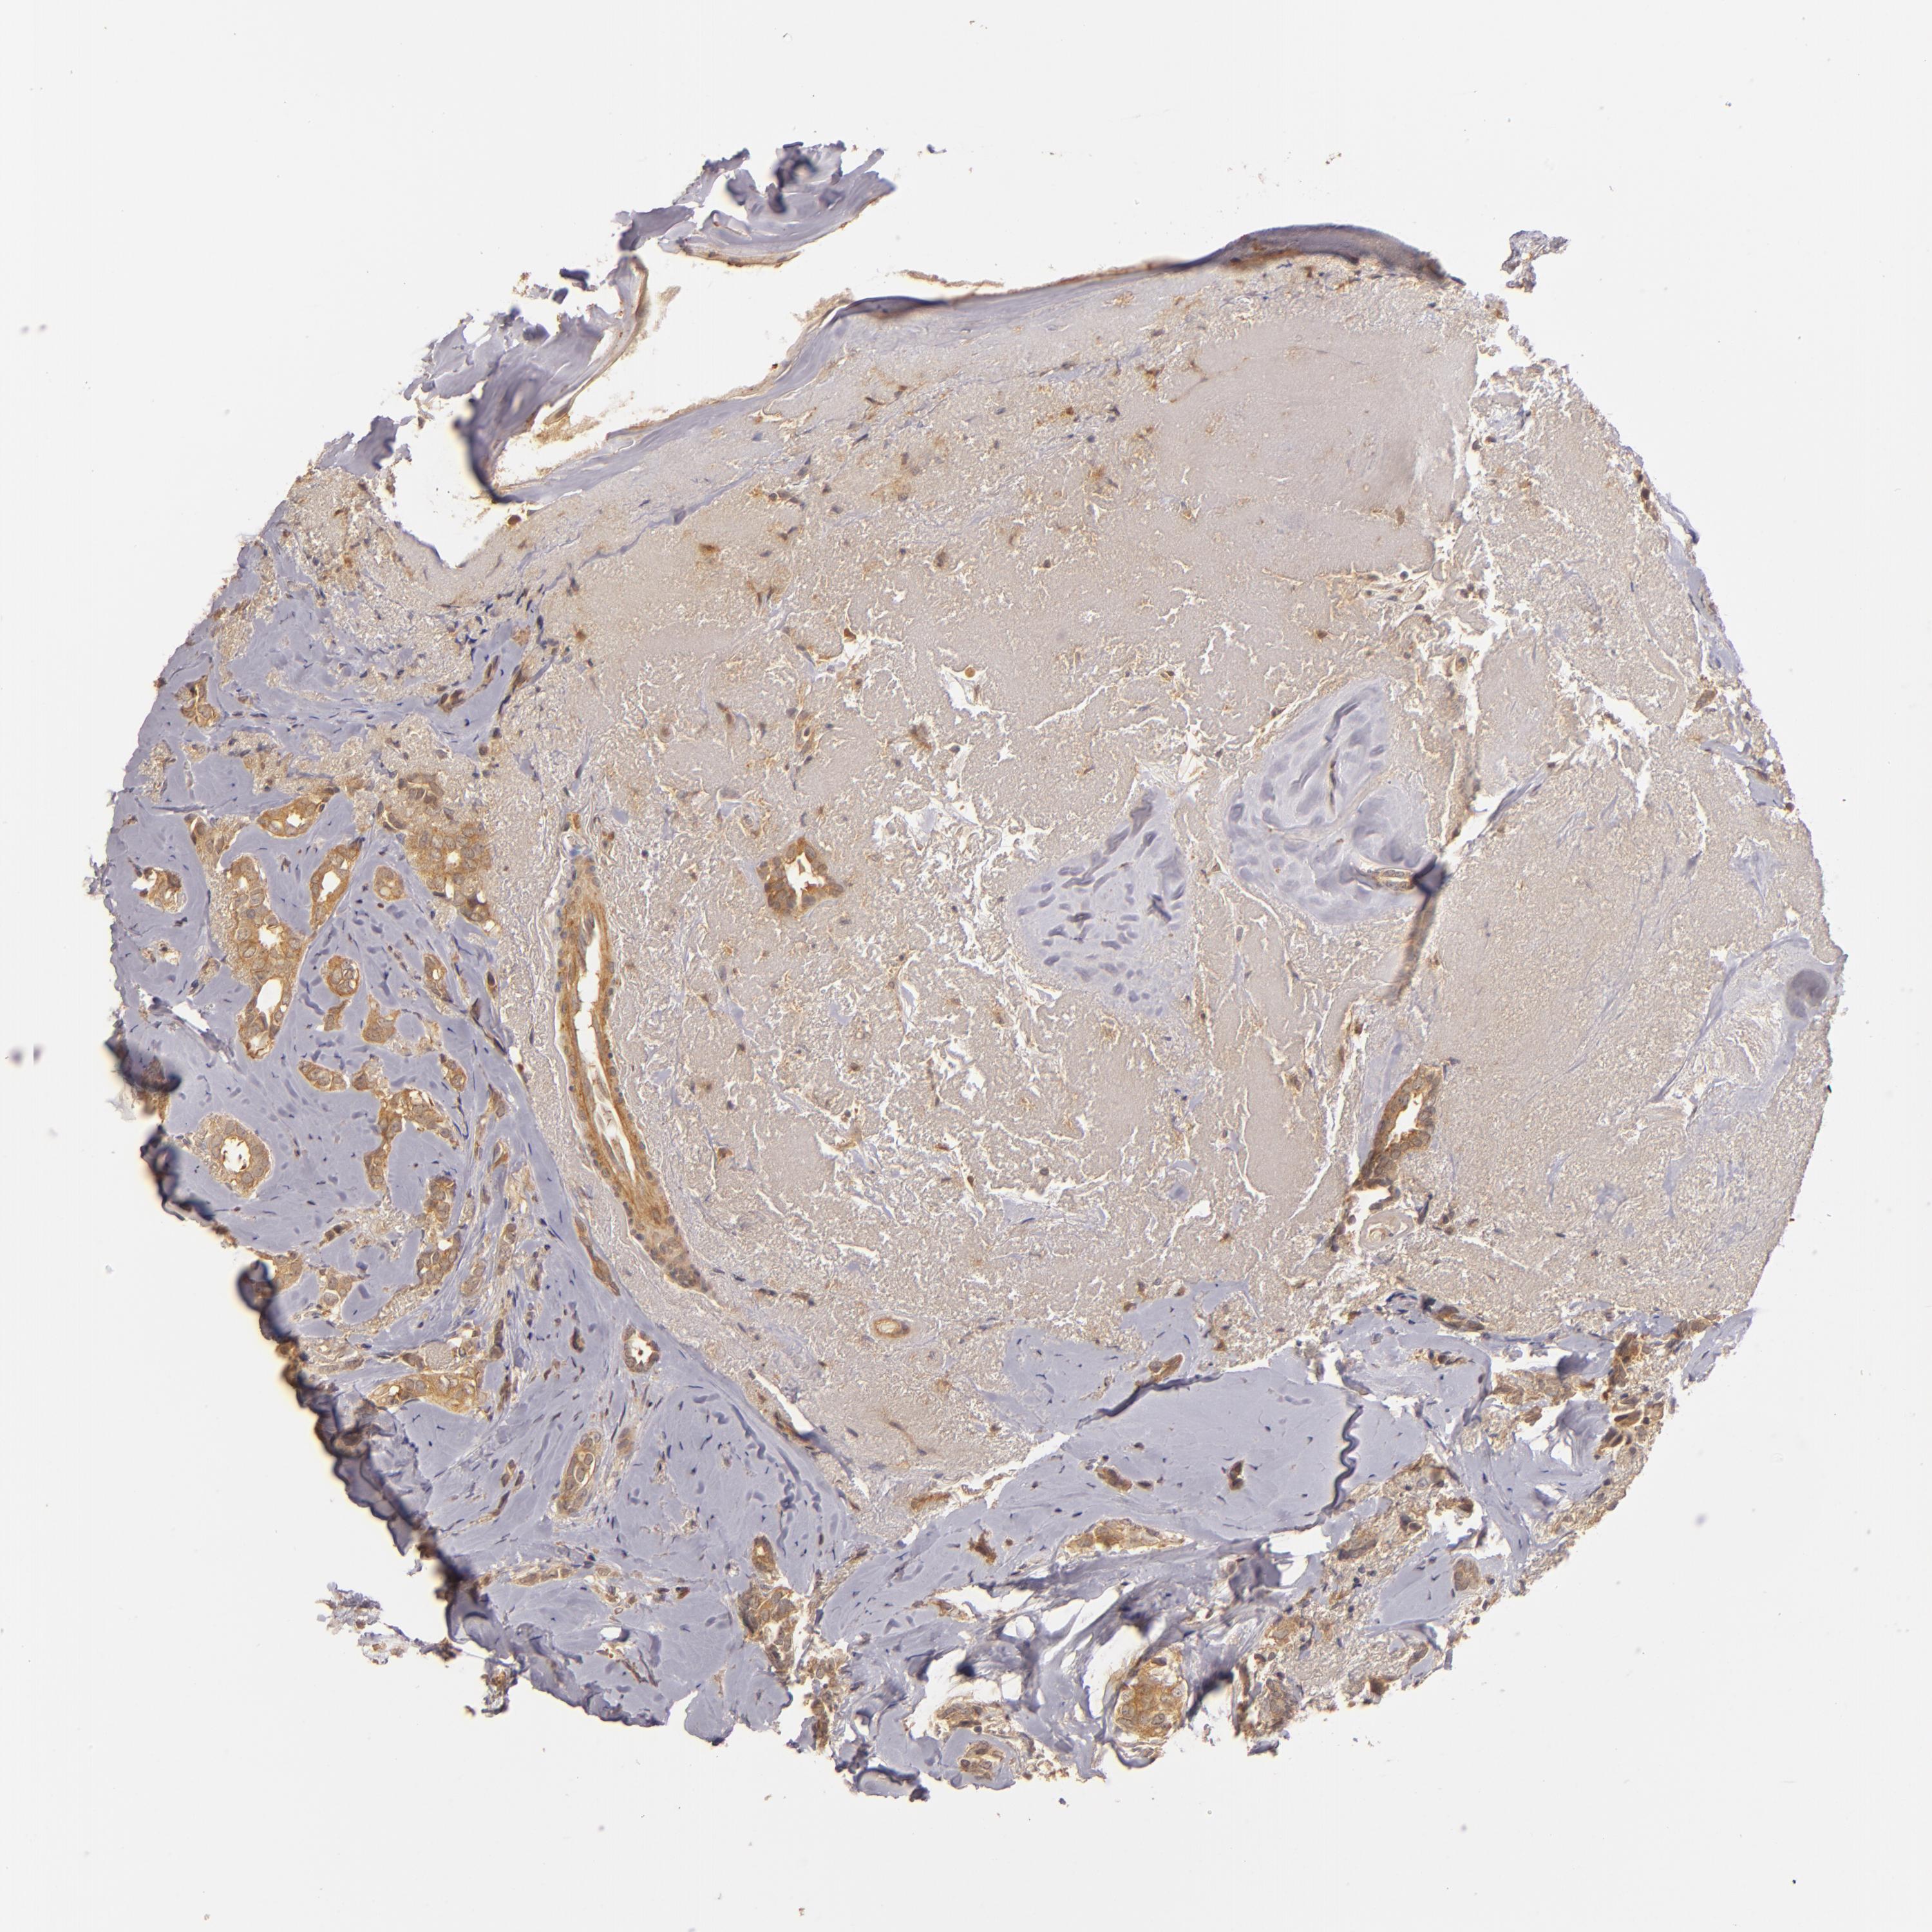

BRCA TCGA BRCA VALIDATION PROTEIN EXPRESSION